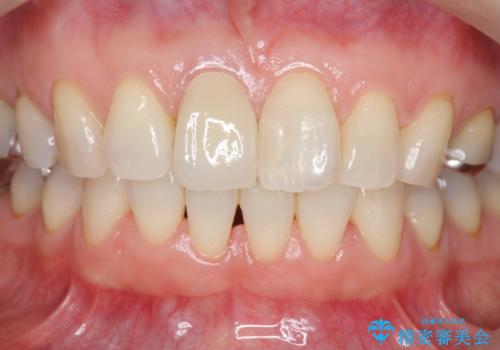

前歯の変色 セラミック審美補綴

- 前歯の変色の改善を希望され来院されました.

以前に神経が死に、根管治療を行った歯の変色が認められたためセラミックによる審美補綴治療を計画します。

- 16万円(仮歯・ファイバーコア・ジルコニアクラウンスペシャル)費用は治療当時の料金となります